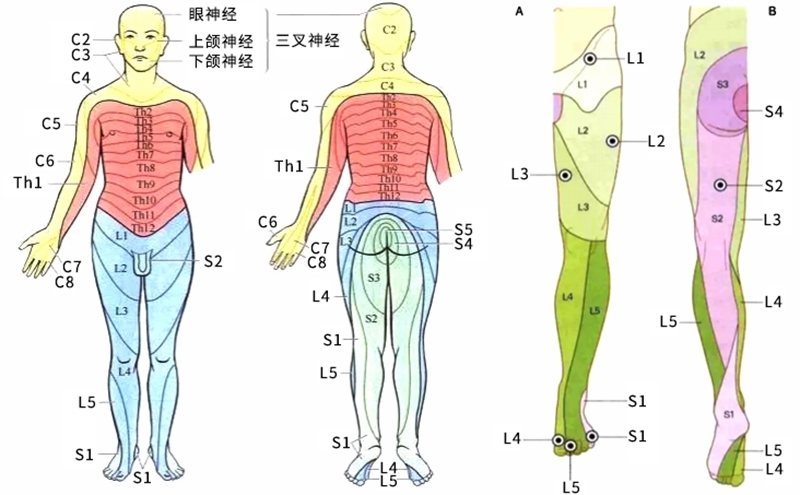

L5神经根解剖

L5神经根是腰椎间盘突出常常累及的神经根。尤其是腰4/5节段的椎间盘突出。临床可从肌力检查、感觉检查及反射检查三个方面来判断L5神经根定位的主要标志性表现。

相关解剖

周围神经病变:L5神经根、坐骨神经、腓总神经、腓深神经、腓浅神经。

患足背伸无力,表现为足下垂畸形,伴或不伴小腿或足背脚趾I-III感觉改变。足背屈、足趾伸展、足外翻和第一蹼间隙感觉丧失无力。踝关节外翻无力。

查体:踝背伸及踇趾背伸肌力3级以下,合并小腿外侧或足背皮肤痛觉减退。